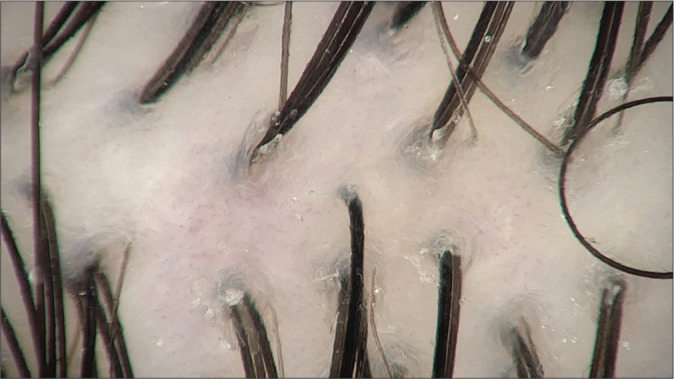

Material and methods: The present cross-sectional observational study was carried out at the Department of Dermatology at a tertiary care center. All the subjects attending the Dermatology Outpatient Department fulfilling inclusion criteria were studied. Data were collected after the approval from the Institutional Ethical Committee. The procedure was explained and a written consent was taken. Each patient's hair was parted in the middle and images from a point of roughly 5 inches from the patient's glabella were taken. The parameters such as hair thickness, hair density, hair count, follicular units, and empty hair follicles/yellow dots were noted.

Results: In the present study, the majority of the study subjects belonged to the age group 26-35 years (38%), followed by 18-25 years (34.7%), 36-45 years (20.7%), and least in the age group of 46-55 years (6.7%). In the present study, the mean unit density in males was 104.78 ± 14.33 and that of females was 108.36 ± 17.60.